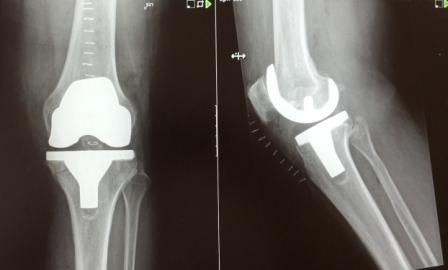

Dr hab. n. med. Ireneusz Babiak - ponad 30-letnie doświadczenie zawodowe zdobywane w trakcie pracy i szkoleń w szpitalach klinicznych w Polsce, Niemczech, Szwajcarii i Szwecji. Specjalizuje się w diagnostyce i leczeniu chorób stawów kolanowych, biodrowych, barkowych, kręgosłupa, deformacji stopy, terapii podciśnieniowej ran (tj NPWT) systemami VAC, Pico, Avelle. Wykonuje operacje: endoprotezy stawu biodrowego i kolanowego ( w ostatnim roku 200 endoprotez implantowanych osobiście i asysta do kolejnych 200 endoprotez), zespół cieśni nadgarstka, palec zatrzaskujący, paluchy koślawe (haluxy), palce młotkowate, zespolenia złamań kości, zaburzenia zrostu, operacje rewizyjne endoprotez stawów, operacyjne leczenie zapaleń kości stawów z zastosowaniem biomateriałów, przeszczepy skóry. Do roku 2017 adiunkt oraz ordynator Oddziału IV w Klinice Ortopedii Traumatologii Warszawskiego Uniwersytetu Medycznego (WUM), oraz wykładowca na English Division Medical University of Warsaw. W roku 2018 stanowisko överläkare - specjalista odpowiedzialny za endoprotezoplastykę biodra i kolana w Klinice Ortopedii w Eskilstunie w Szwecji. Wykładowca na kursach szkoleniowych z operacji rewizyjnych endoprotez stawów, zapaleń kości i stawów, planowania w endoprotezoplastyce stawów, powikłań w ortopedii. Członek towarzystw naukowych: PTOiTr (Polskie Towarzystwo Ortopedyczne i Traumatologiczne), EBJIS (European Bone and Joint Infection Society), PTZS (Polskie Towarzystwo Zakażeń Szpitalnych).

Zdjęcia i filmy